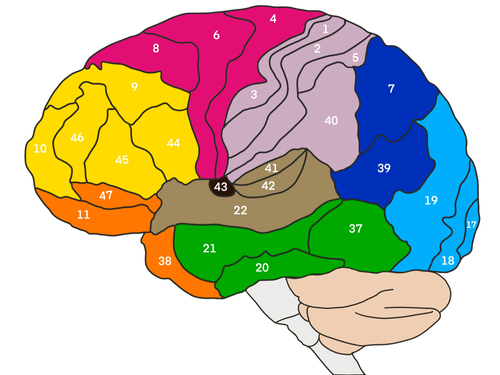

The Influence of Psychological Factors on Outcomes Following Wrist and Hand Injuries: A Systematic Review

The Influence of Psychological Factors on Outcomes Following Wrist and Hand Injuries: A Systematic ReviewArticle: Minnucci, S., Fochi, F., Lerose, E., Scalise, V., & Brindisino, ...

手外伤患者发生复杂区域疼痛综合征 (CRPS) 的危险因素

参加手部治疗的患者的手部创伤和 CRPS 作者:Tristany Hightower Savaş, S., Ánal, EE, Yavuz, DD, Uslusoy, F., Altuntaş, SH, ...